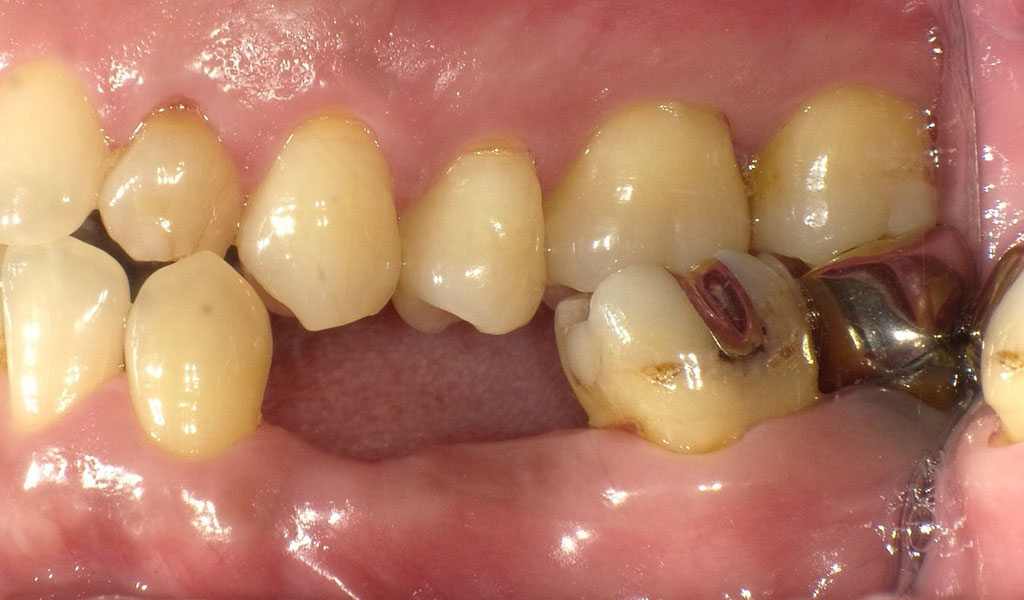

40代男性・横浜市在住。5年前に左下5番が抜け、左下4番からブリッジをかけていたが左下4番が2ヶ月前に抜けてしまい、インプラントを入れるために当院を受診。当院にて左下4番、5番に、インプラント治療。人工歯はジルコニア人工歯。スクリューリテインにて固定しました。左下4番については歯根が残ったままだったので、抜歯を実施。

Before2

After2

40代男性・横浜市在住。5年前に左下5番が抜け、左下4番からブリッジをかけていたが左下4番が2ヶ月前に抜けてしまい、インプラントを入れるために当院を受診。

治療内容

術前検査(歯周病菌の検査(PCR検査))を行ったところ、Pg菌、Td菌、Tf菌の数値が高かったため、投薬及びクリーニングによる歯周病内科治療を実施。

左下4番の歯根が残っていたため、抜歯。通常手術にて、左下4,5番の骨にインプラントを埋め込みました。

歯周内科治療終了後、再PCR検査によりPg菌、Td菌、Tf菌の数値が問題ないレベルまで下がったことを確認。

インプラントと骨がしっかり結合するまで術後3ヶ月待ち、インプラントの上に人工の歯を被せる治療を行いました。